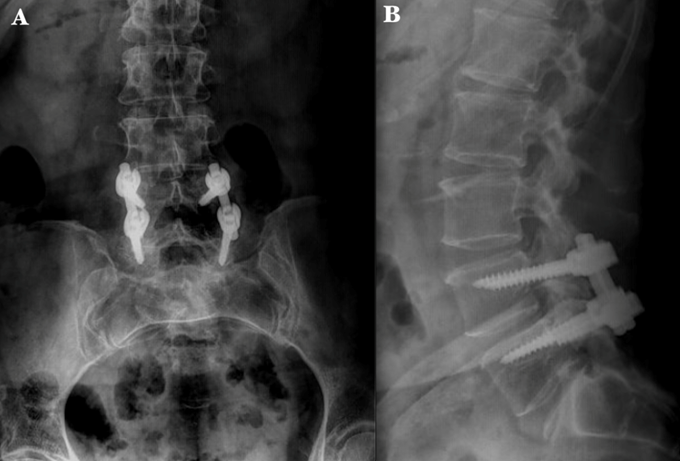

61-year-old female, with type 2 diabetes mellitus, spinal surgery in 2017 in which a discectomy and transpedicular instrumentation of L4-L5 was performed. Presented herself into the ER with a history of low back pain and related left leg symptoms which increased with lumbar flexion and extension of 8 months of evolution. Physical examination showed limp gait, left paravertebral muscular contracture, hyperesthesia, and nerve root irritation. Implant fatigue was evident (Figure 1 & 2). A standard posterior approach to lumbar spine was performed, the rods were removed, identifying the fatigue of the right L5 transpedicular screw, the polyaxial head was then removed with a plier to expose the broken screw head. Then, the rest of the screws were removed with torx screwdriver. Subsequently the interbody cages L3-S1 were inserted with TLIF technique in addition to transpedicular instrumentation (L3-L4-S1 right; L3-S1 left) (Figure 3). After surgery, the patient showed an immediate improvement, decreased pain and absence of leg symptoms. She started to walk 8 hours after the surgery, and she was discharged 20 hours later without complications.

Figure 3 Intraoperative fluoroscopic images A) Anteroposterior image shows the left L3-S1, L3-L4, and right S1 transpedicular instrumentation and the distal portion of the broken L5 screw. B) Lateral image shows proper placement of transpedicular screws and interbody cages at L3-S1levels. .